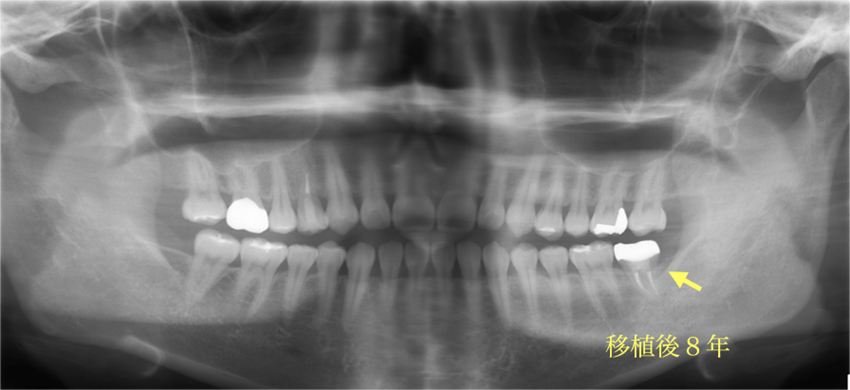

親知らずを移植し咬み合わせを作ったケースの症例紹介

Before

抜歯後1ヶ月で親知らずの抜歯を行った

移植歯の根管治療終了時

After

ジルコニアで修復

主訴

奥歯がたまに痛い

治療内容

パーフォレーションの起きていた歯は温存困難だったため抜歯を行い、その後1ヶ月後に親知らずの移植を行った。移植後に根管治療を行いその後ジルコニアで補綴を行った。

治療費

20万円(税込)

治療期間

5ヶ月

治療回数

12回

想定されたリスク

※移植歯が定着しないリスクや、今後移植歯が外部吸収やアンキローシスを起こす可能性がありました。

中山亮平先生

戸越なかやま歯科

歯を抜歯した後の補綴処置として移植治療はとても効果的であり、特にこの方のように20代など若い場合には当院ではインプラント治療よりも移植治療を勧めており、インプラント治療の先延ばしを考えている。ただし大きさや形によっては予後が不良になる場合もあるので術前のCBCTによる診断がとても大切である。